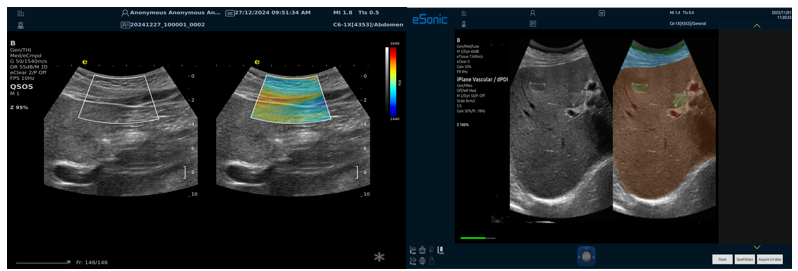

RTSWE实时剪切波弹性成像

?探头发射激励脉冲进行多点动态聚焦,利用马赫圆锥原理,形成大量的剪切波信号?颜色的变化与剪切波的速度相关,可直接体现肌肉肌腱等组织硬度值?实时、全幅、全定量

肌骨png.png

鉴别诊断、精准分级、定量评价、穿刺引导、疗效评估、随访观察